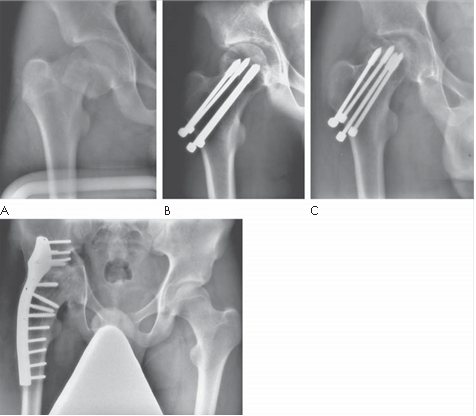

Describe the abnormalities you see on these radiographs. What is the likely diagnosis?

These AP and lateral radiographs show sessile lesions arising from the metaphyseal region of the distal femur. The lesions are well defi ned and appear to be growing away from the metaphysis. The matrix of the lesions is in continuity with the surrounding normal bone. The cortex of the normal bone appears to be in continuity with the lesions. The caps of the lesions contain fl ecks of calcifi cation. These appearances would be compatible with a slow-growing, benign lesion, most likely osteochondroma.